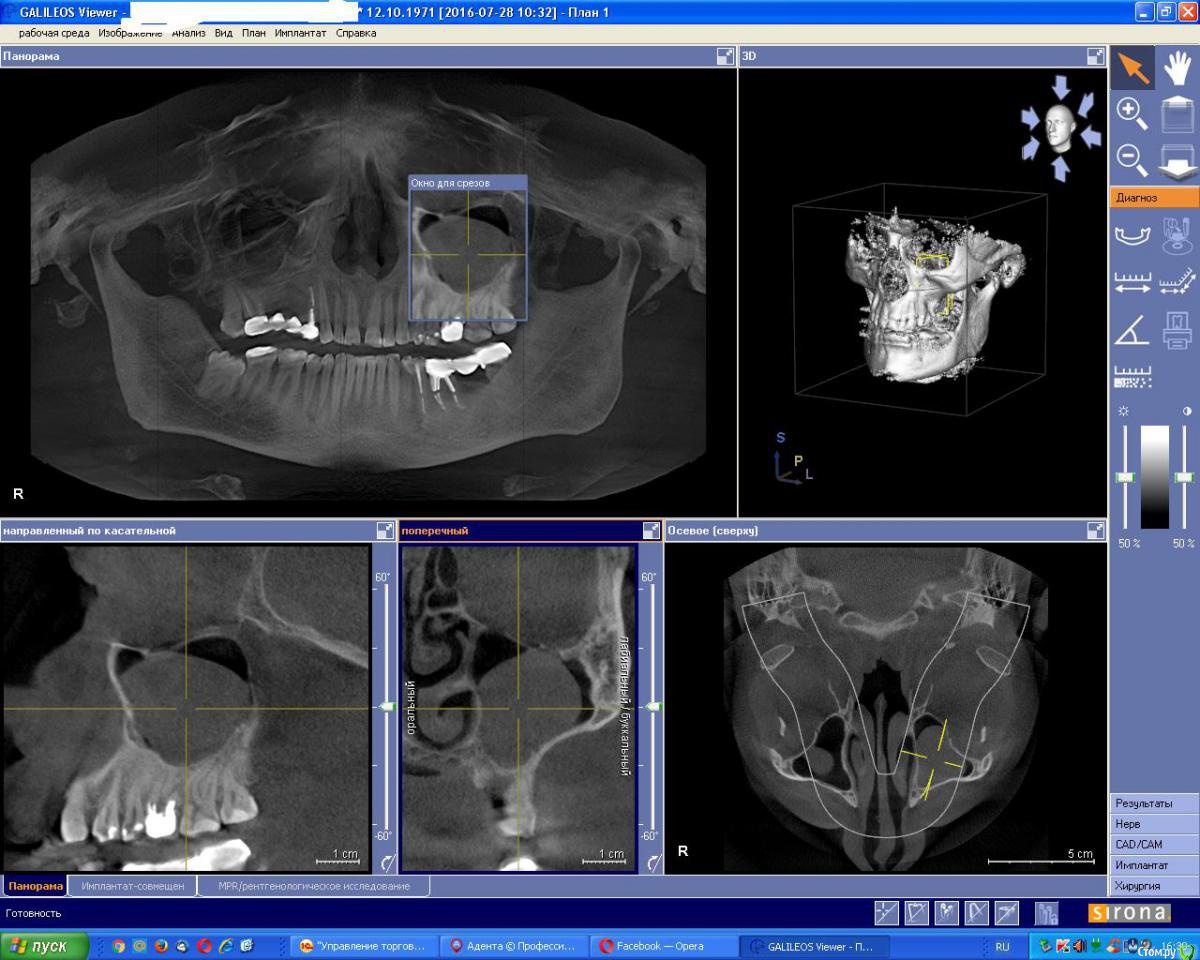

an_ver Опубликовано 29 июля, 2016 Поделиться Опубликовано 29 июля, 2016 Вот такой пузырь обнаружил у своего техника(((...как убрать? Меньше размером убирал..такое мешок еще нет Ссылка на комментарий

kriokov Опубликовано 29 июля, 2016 Поделиться Опубликовано 29 июля, 2016 не думаю , что это радикулярная киста, как таковая1. нет деформации наружной кортикальной пластинки 2. не характерной для радикулярной тонкой кортикальной над куполом образования в пазухе Думаю , что есть деструктивные изменения в обл 26, частично ушла кортикальная дна синуса. Вторично , как следствие воспалительного процесса возникла ретенционная из желез слизистой синуса.Удалил бы 26, ревизия , отпунктировать и "отсосать" содержимое образования , оболочка должна отойти. Потом закрыться с неба. И если можно, два среза КТ - аксиальный и корональный на уровне нижнего края орбиты , где вершина купола 3 Ссылка на комментарий

___49___ Опубликовано 29 июля, 2016 Поделиться Опубликовано 29 июля, 2016 (изменено) На мой взгляд это мягкотканное образование не имеющее полости и жидкого содержимого .....напоминает больше полип(или другое подобное по структуре новообразование) нежеле радикулярную кисту... если нет нарушения кортикалки - удалил бы 26 при наличии показаний , а дальше к ЛОРам .... Ниже снимок кисты - визуализируется оболочка, и полость разной рентген контрастности. Изменено 29 июля, 2016 пользователем ___49___ Ссылка на комментарий

an_ver Опубликовано 30 июля, 2016 Автор Поделиться Опубликовано 30 июля, 2016 не думаю , что это радикулярная киста, как таковая1. нет деформации наружной кортикальной пластинки 2. не характерной для радикулярной тонкой кортикальной над куполом образования в пазухе Думаю , что есть деструктивные изменения в обл 26, частично ушла кортикальная дна синуса. Вторично , как следствие воспалительного процесса возникла ретенционная из желез слизистой синуса.Удалил бы 26, ревизия , отпунктировать и "отсосать" содержимое образования , оболочка должна отойти. Потом закрыться с неба. И если можно, два среза КТ - аксиальный и корональный на уровне нижнего края орбиты , где вершина куполаДумаю хрень поперла от небного корня,есть вроде сообщение.И в 10-м сегменте такая же зреет Ссылка на комментарий

Чертков Александр Опубликовано 1 августа, 2016 Поделиться Опубликовано 1 августа, 2016 Андрей, а связь образования с нижней стенкой орбиты не смущает?....сужу чисто по срезам, но как то уж очень "интересно" прилегает....точечно и при этом вроде как "свисает", не? Ссылка на комментарий

an_ver Опубликовано 1 августа, 2016 Автор Поделиться Опубликовано 1 августа, 2016 Андрей, а связь образования с нижней стенкой орбиты не смущает?....сужу чисто по срезам, но как то уж очень "интересно" прилегает....точечно и при этом вроде как "свисает", не?Вот поэтому то и сюда выставил картинки,что смущает...но на другой стороне структура ниж.стенки такая же... Ссылка на комментарий